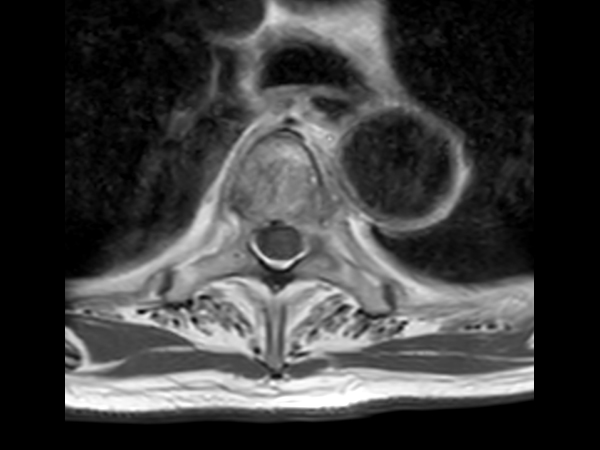

Axial T2w TSE (T4)